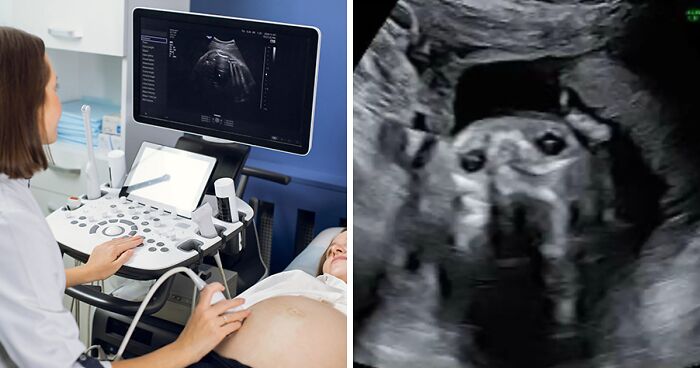

Inês Egner, an influencer and soon-to-be mother from Portugal, couldn’t believe her eyes when her 20-week anatomy scan revealed something unexpected, and hilarious.

Instead of her baby, the machine showed what appeared to be the face of her dog, Goulash, staring back at her.

A mother went viral after sharing the results of her 20-week anatomy scan: her unborn son looked exactly like her beloved pet dog

As for what created the strange, dog-like image. Egner explained to her viewers that it was most likely the result of a weird angle.

“They were checking from the angle of his chin, checking up his nostrils and his eyes,” she said.